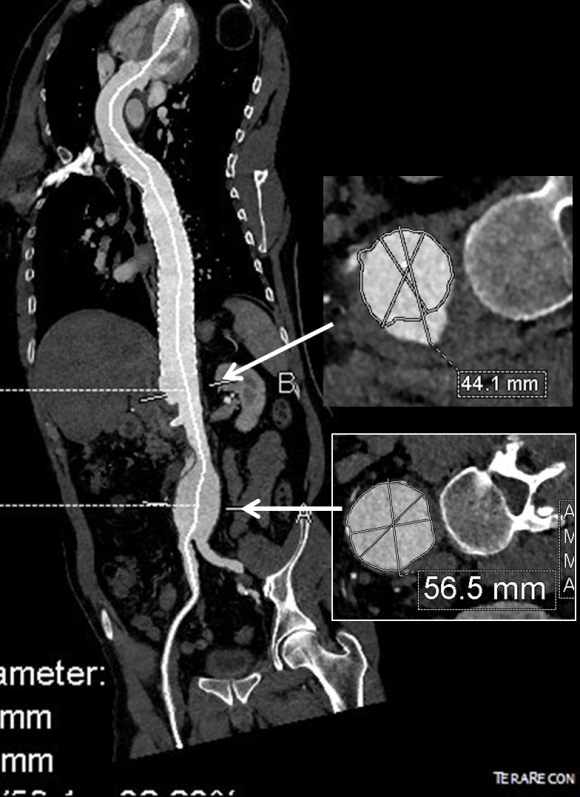

This patient presents with lifestyle limiting claudication and an absent right femoral pulse. ABI is moderately reduced on the right to 0.57, and he had no rest pain. CTA at our clinic revealed an occluded EIA bracketed by severely calcified and nearly occlusive plaque of the common iliac artery (CIA) and common femoral artery (CFA).

This has several advantages over conduit creation which can be a morbid and high risk procedure in patients who require minimally invasive approach. A graft is avoided. The artery is over 8mm in diameter where with stenting up to 8mm with an occlusive plaque, the danger of rupture is present, and often ballooning is restricted to 6mm-7mm. This is insufficient for many TEVAR grafts and TAVR valves.